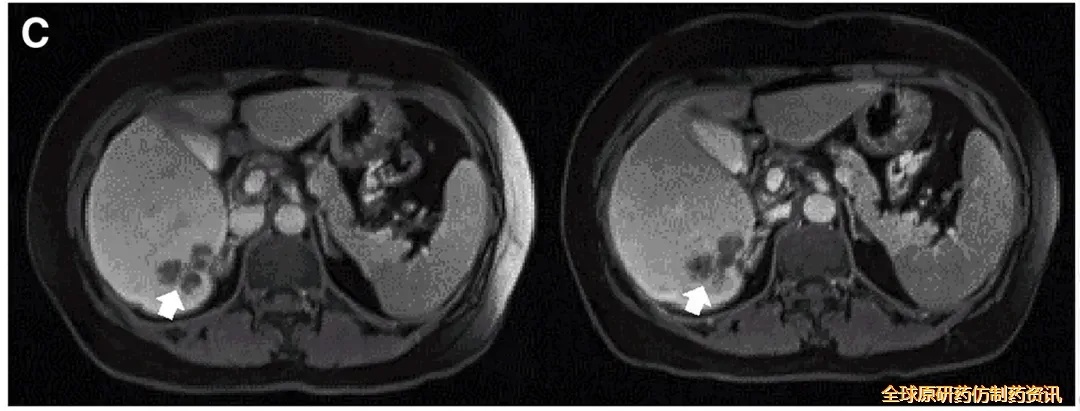

值得一提的是,典型病例P10在接受DL4剂量CEA CAR-T治疗后,MRI检查证实肝内一处病灶明显缩小(详见下图)。

▼P10患者在CAR-T治疗前(左图)、治疗4周后(右图)的MRI对比

▲图源“Molecular Therapy”,版权归原作者所有,如无意中侵犯了知识产权,请联系我们删除